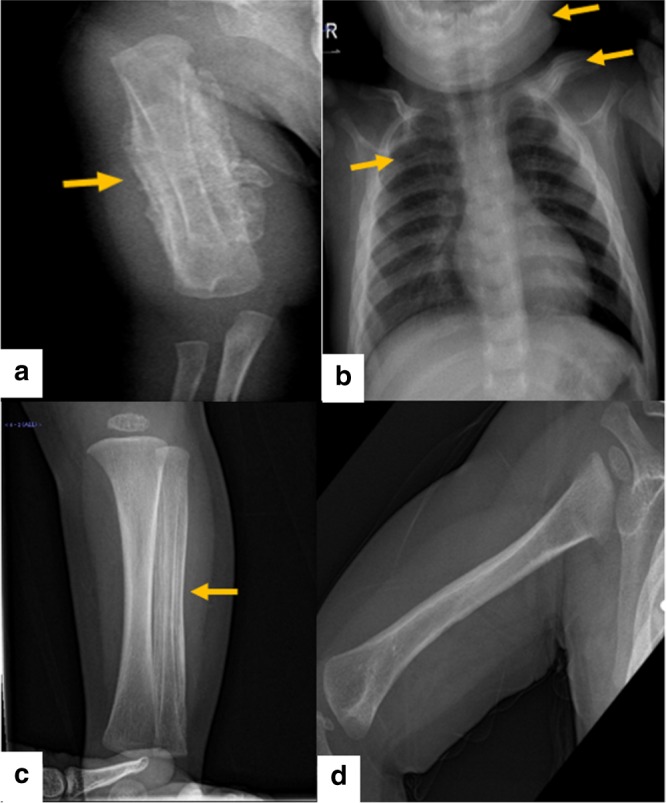

對(duì)右臂進(jìn)行 X 光檢查,顯示沿右肱骨的整個(gè)骨干骨膜反應(yīng)旺盛(圖 1a)。 進(jìn)一步評(píng)估包括 X 線(xiàn)骨骼檢查,顯示一側(cè)肩胛骨、一根腓骨、下頜骨和許多肋骨有明顯的骨膜反應(yīng)(圖 1b)。 根據(jù)臨床和放射學(xué)檢查結(jié)果,診斷為 ICH。 盡管德托尼-卡菲病可能具有短暫性,但開(kāi)始使用吲哚美辛(每天 5mg/kg)治療,并且病變?cè)趲讉€(gè)月內(nèi)有效消失,正如后續(xù)放射學(xué)檢查所證明的那樣(圖 1c)。 經(jīng)過(guò) 1 年的隨訪(fǎng),患者有效康復(fù),沒(méi)有骨骼畸形和/或升高的炎癥標(biāo)志物。 他仍在服用低劑量的消炎痛(每天 1mg/kg)。

患者的射線(xiàn)照相檢查。 a 沿右肱骨整個(gè)軸的骨膜反應(yīng)。 b 沿左鎖骨、肋骨和下頜骨的骨膜反應(yīng)。 c 沿腓骨的骨膜反應(yīng)。 d 肱骨骨膜有效消退